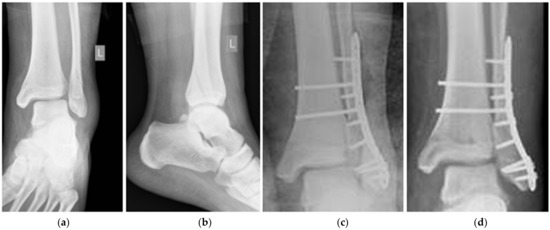

Deformation of the Titanium Plate Stabilizing the Lateral Ankle Fracture Due to Its Overloading in Case of the Young, Obese Patient: Case Report Including the Biomechanical Analysis

2.1. Patient and the History of Treatment